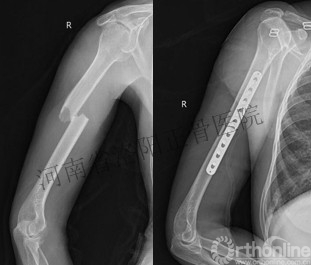

肱骨干骨折,骨折端横向错位,行手术治疗,术中解剖复位骨折钢板螺钉固定并断端加压,术后X线复查可见骨折线几乎完全消除。